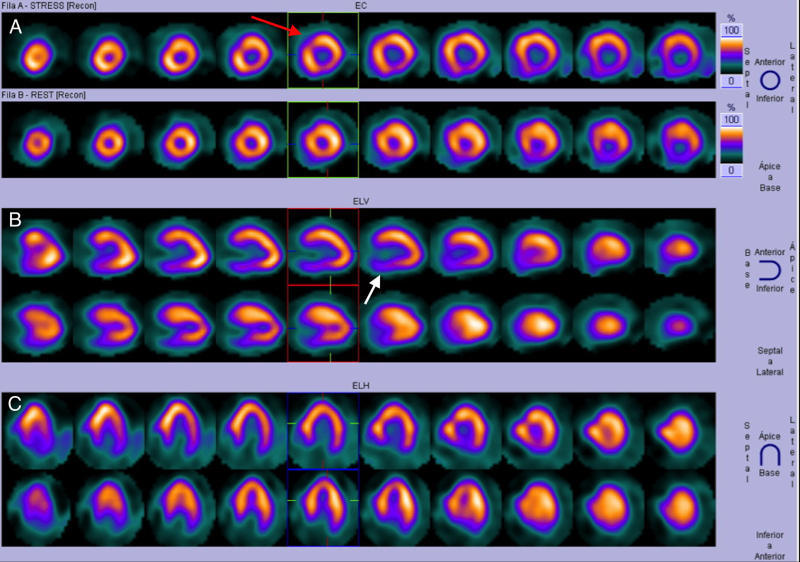

Estudio de perfusión miocárdica Gated-SPECT con 99mTc-MIBI en fases post-estrés (A) y reposo (B). Valoración de contractilidad y cálculo de parámetros funcionales. Se observa la cavidad ventricular izquierda aumentada de tamaño post-estrés (confirmando los hallazgos de los cortes en las figuras previas). La fracción de eyección calculada post-estrés fue de 40% y en reposo de 57%.

Ante estos hallazgos, se decidió realizar estratificación de riesgo mediante gammagrafía de perfusión miocárdica Gated-SPECT (estudio tomográfico sincronizado con electrocardiograma) con 99mTc-MIBI (dosis total 24 mCi) bajo protocolo de esfuerzo físico y reposo de 2 días. Las imágenes evidenciaron hipocaptación moderada en los segmentos basal y medial de las caras inferior e inferolateral del VI y en el segmento medial de la cara anteroseptal en el estrés, con reversión completa en el reposo. El resultado fue catalogado como isquemia inducida en los segmentos mencionados (figura 1), a lo que se asoció dilatación ventricular durante el estrés con TID (dilatación isquémica transitoria) calculada en 1,28 (valores considerados normales < 1,19) (figuras 2 y 3), fracción de eyección en el reposo de 57% que cayó a 40% post-estrés y deformidad parcial del septum basal.